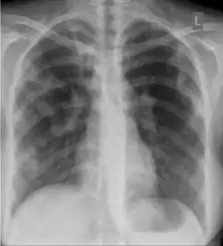

Radiology (X-rays) is used in the diagnosis of tuberculosis. Abnormalities on chest radiographs may be suggestive of, but are never diagnostic of TB, but can be used to rule out pulmonary TB.

A posterior-anterior (PA) chest X-ray is the standard view used; other views (lateral or lordotic) or CT scans may be necessary.

In active pulmonary TB, infiltrates or consolidations and/or cavities are often seen in the upper lungs with or without mediastinal or hilar lymphadenopathy.[1] However, lesions may appear anywhere in the lungs. In HIV and other immunosuppressed persons, any abnormality may indicate TB or the chest X-ray may even appear entirely normal.[1]

Abnormalities on chest radiographs may be suggestive of, but are never diagnostic of, TB.[1] However, if a person has a positive response to the tuberculin skin test and no symptoms of the disease, chest radiographs can be used to rule out the possibility of pulmonary TB.